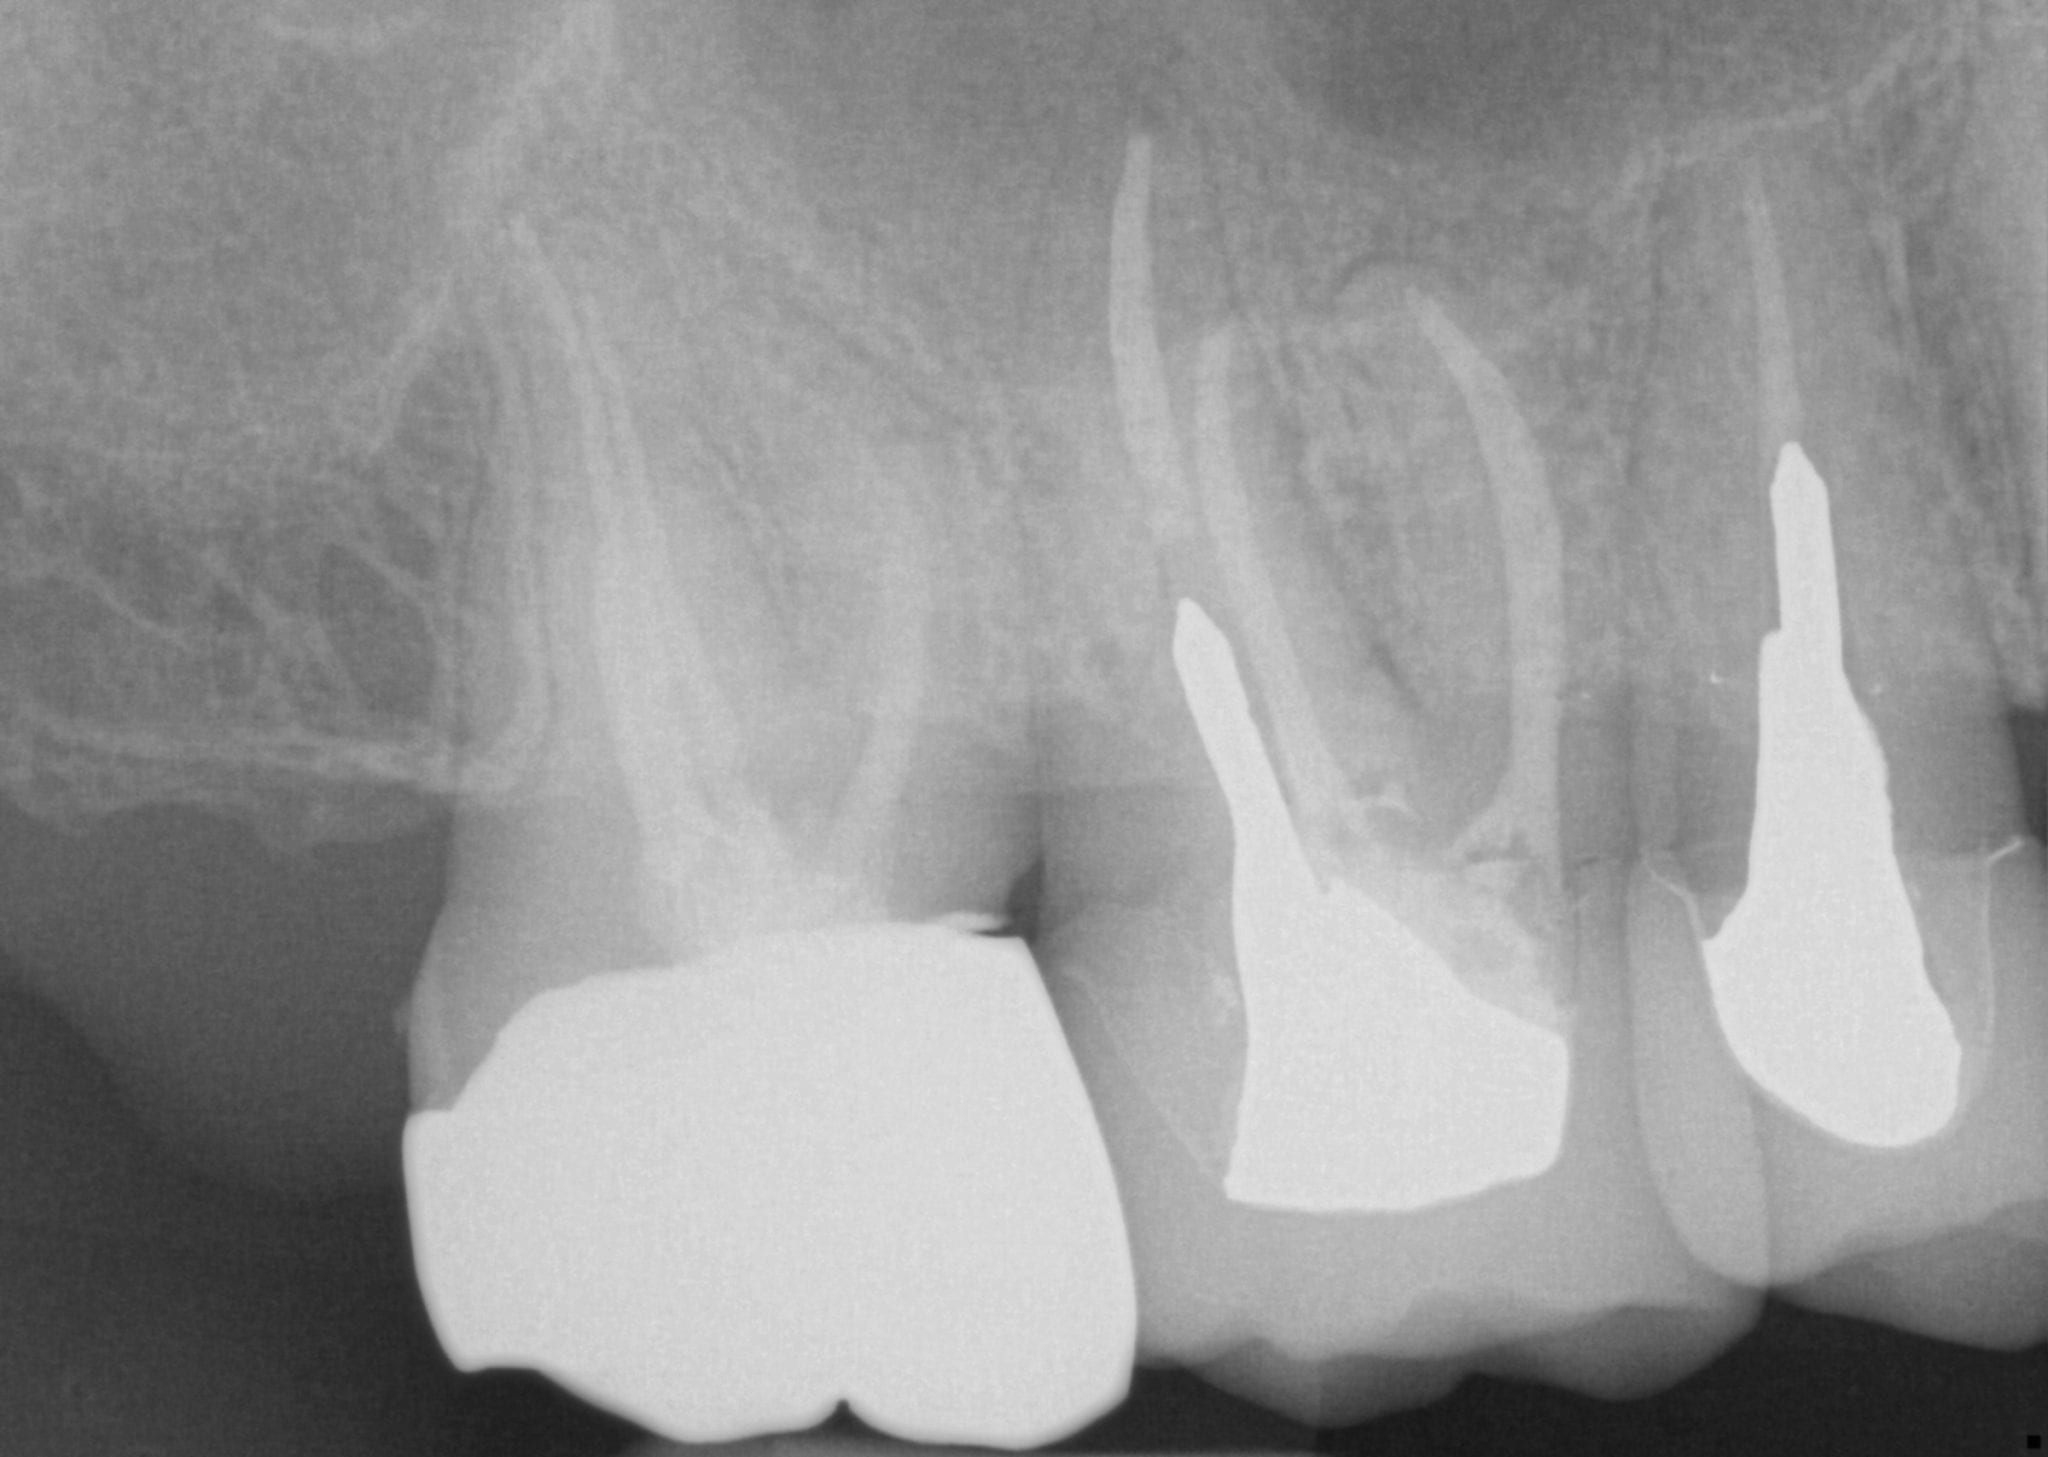

One Month Post Op with Radiographs